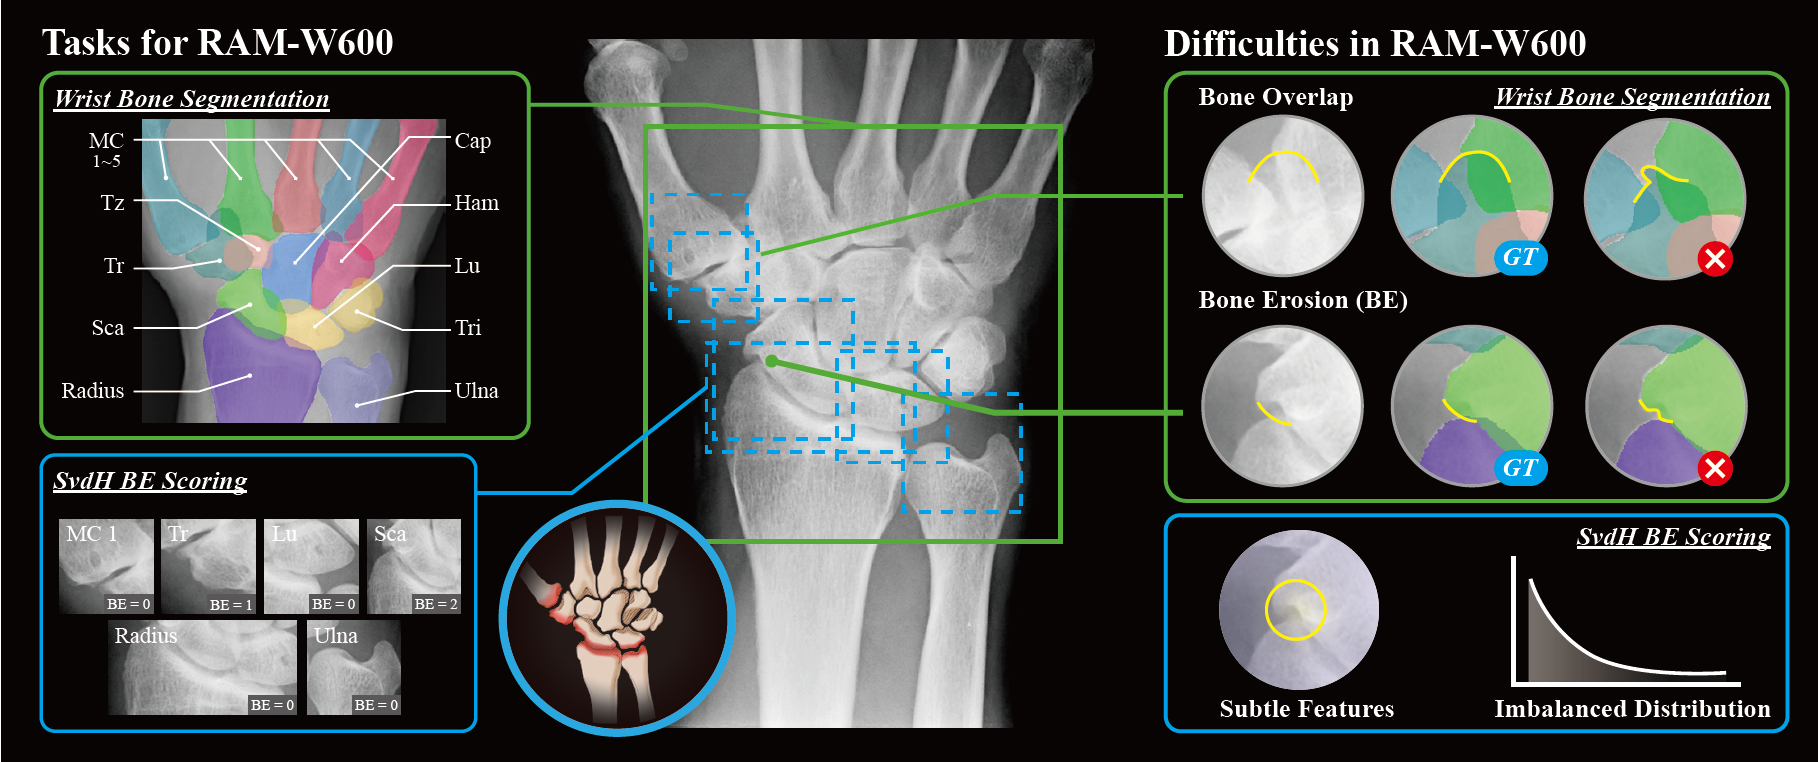

RAM-W600: A Multi-Task Wrist Dataset and Benchmark for Rheumatoid Arthritis)

Songxiao Yang, Haolin Wang, Yao Fu, Ye Tian, Tamotsu Kamishima, Masayuki Ikebe, Yafei Ou, Masatoshi Okutomi